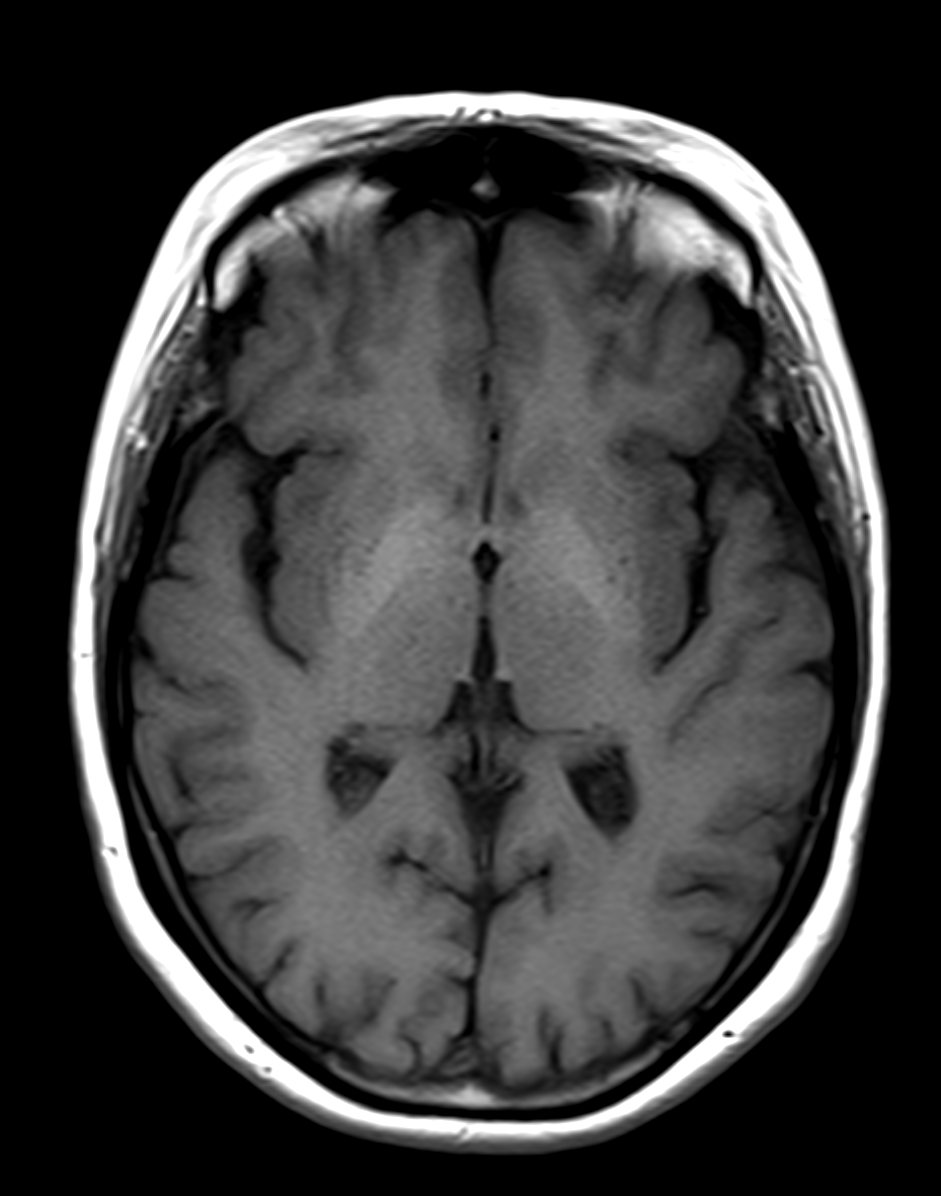

Results: A 58 years old female patient with a medical history of depressive disorder, type 2 diabetes mellitus, hypothyroidism, and autoimmune hepatitis presented with recurrent falls over the past year. Her neurological examination identified an ataxic gait as the sole abnormality. Magnetic resonance imaging (MRI) of the brain demonstrated hyperintensity on T1-weighted sequences in the globus pallidus [Figure 1], interpreted as indicative of manganese deposition resulting from chronic liver disease. The patient received a diagnosis of AHD. Her mother had a documented history of ataxia and late-onset chorea. Genetic testing confirmed HD in the mother. Genetic testing for the patient revealed an expansion of 44 CAG repeats in one allele and 17 repeats in the other allele.

Brain MRI. High T1 signal in the globi pallidi